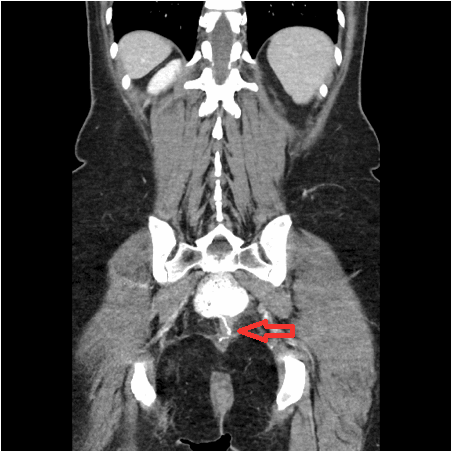

Figure 3. Arrow noting distal pouch narrowing with proximal dilation due to torsion (2018)

One year later, in July 2018, she began developing similar obstructive symptoms. She had a CT scan (Figure 2 and Figure 3) and underwent a flexible pouchoscopy (Figure 4), which again revealed torsion of the pouch. A red-rubber catheter was inserted into the pouch decompression and temporary relief of symptoms. After a period of bowel rest and resuscitation, she was taken to the operating room for exploration.